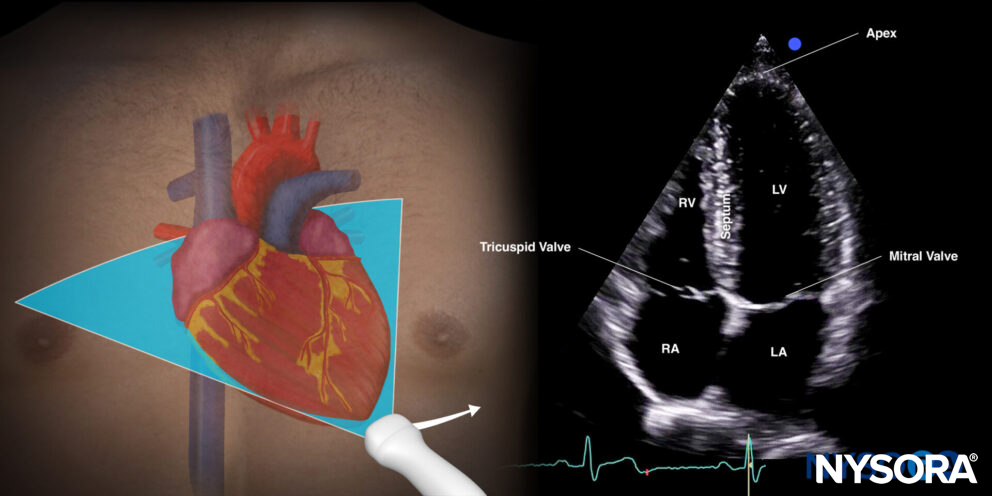

The apical four-chamber view cuts the heart through the coronal plane.

Sonoanatomy of the heart in the apical four-chamber view. Left atrium (LA), left ventricle (LV), right atrium (RA), right ventricle (RV), septum, tricuspid valve, mitral valve, apex.

Reverse ultrasound anatomy:

Reverse Ultrasound Anatomy of the heart in the apical four-chamber view. Left atrium (LA), left ventricle (LV), right atrium (RA), right ventricle (RV), septum, tricuspid valve, mitral valve, apex.